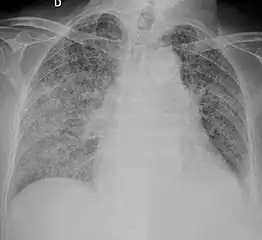

X-ray, showing bilateral interstitial infiltrates